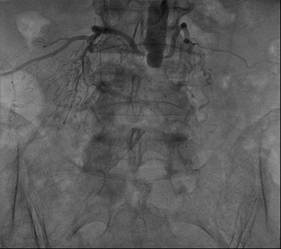

Trước nguy cơ cắt cụt chi nếu không tái thông mạch máu nuôi dưỡng mà trực tiếp là động mạch chậu chung; bệnh nhân N.T. được ekip các bác sĩ tiến hành can thiệp đặt stent động mạch chậu chi dưới qua da bằng ống thông động mạch. Ca can thiệp được thực hiện thành công ngoài mong đợi.

Trước khi đặt Sten |